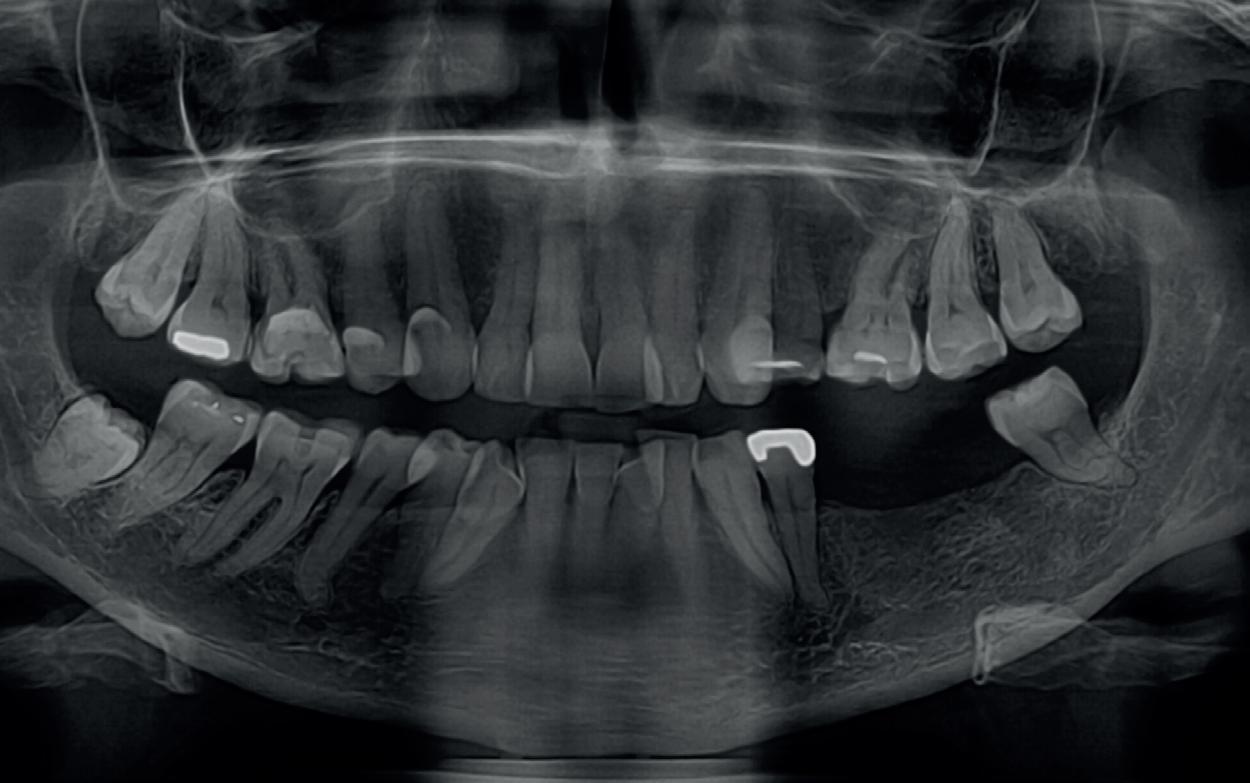

Bij klinisch en röntgenologisch onderzoek viel echter op dat radix van de 12 en 22 een convergerende (de radices staan dan naar mesiaal en naar elkaar toe) in plaats van divergerende (radices staan dan van elkaar af) stand had. Door deze convergerende stand van de radices was er in mesio-distale zin geen ruimte voor twee implantaten ter plaatse van de 11 en 21. Er werd daarom besloten, in tegenzin

2. OPT radices 12 en 22 convergeren

4. OPT radices 12 en 22 divergeren na orthodontische behandeling